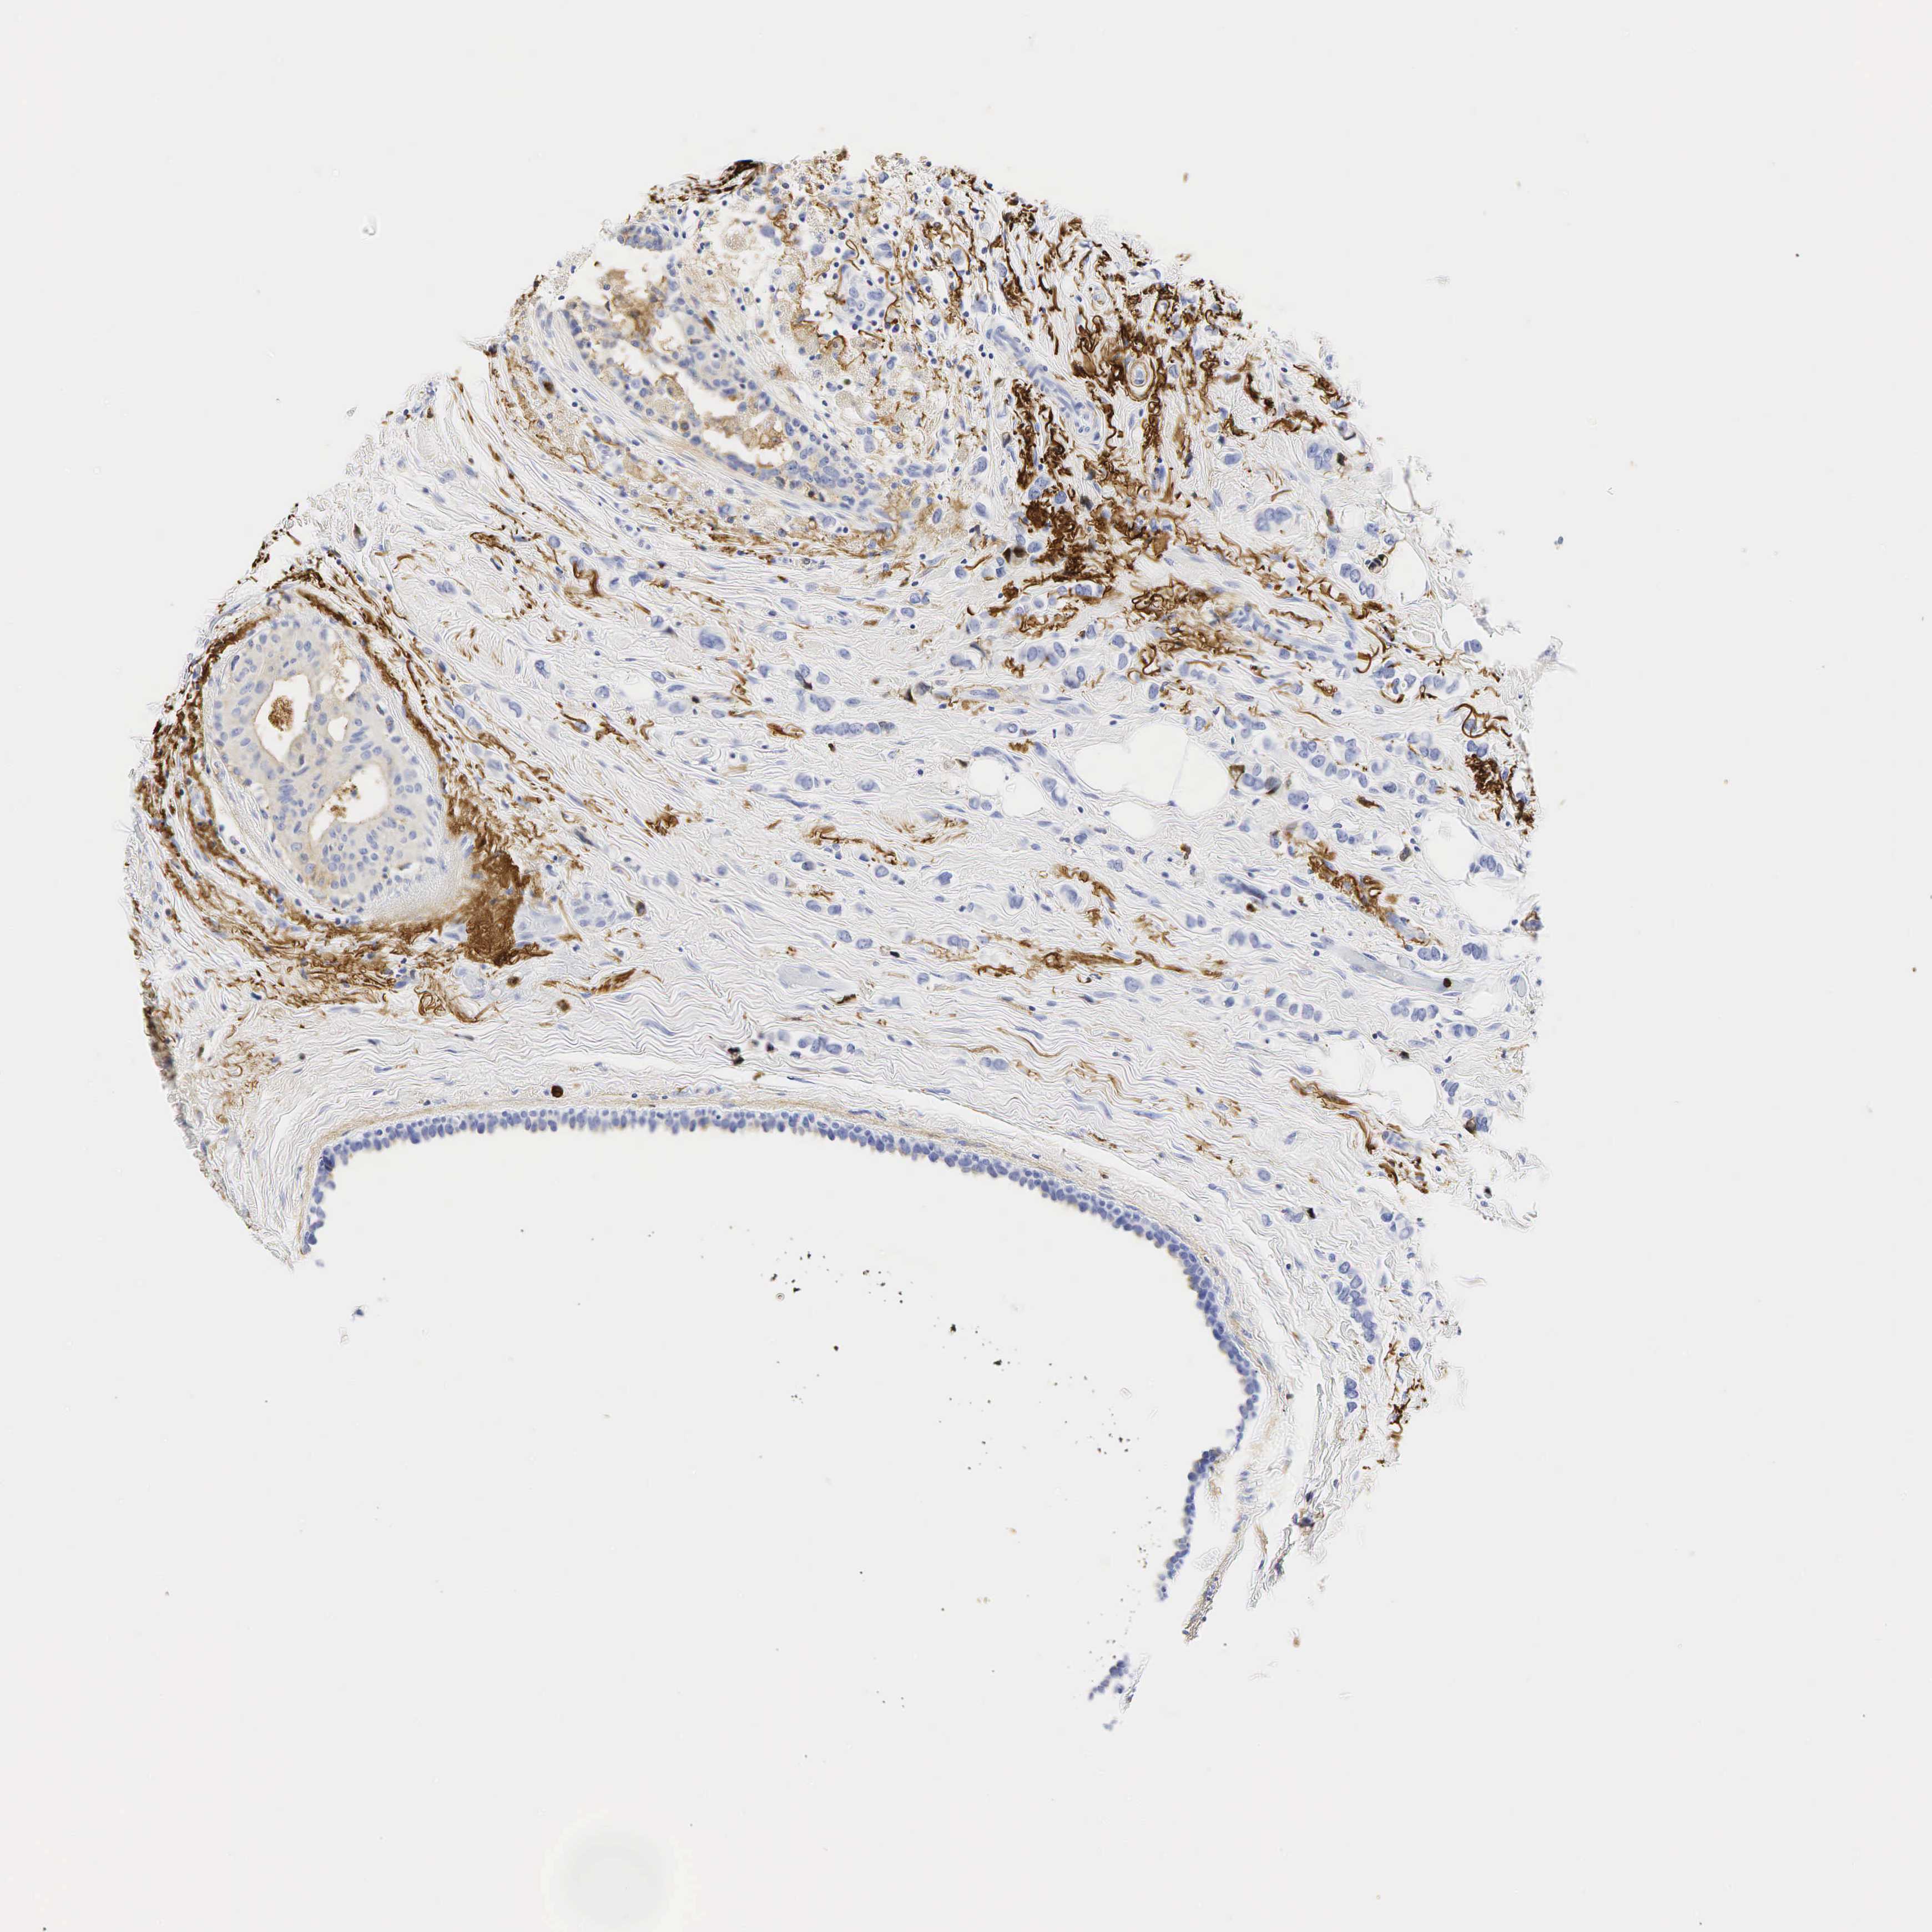

BRCA TCGA BRCA VALIDATION PROTEIN EXPRESSION

ANTIBODIES

AND

VALIDATION